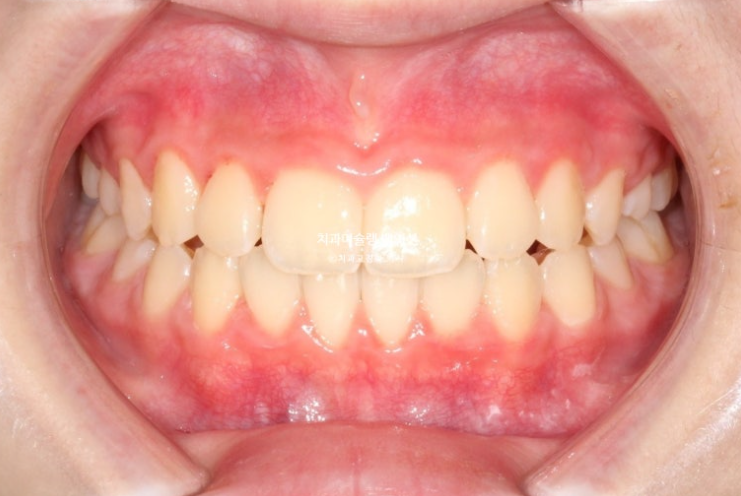

25년 6월 드디어 치료를 마무리 했습니다.

25.06

중심선은 잘 맞습니다.

아직 작은어금니들이 좀 더 내려와야 교합이 안정됩니다.

23.06~25.06

남아있는 유치는 없고 완전한 영구치열에 접어들었습니다.

나중에 2차교정을 안해도 될 정도가 되었습니다.

좋은 결과를 오래 유지하기 위해서 철사 고정식 유지장치 및 가철식 유지장치까지 꼼꼼하게 들어갑니다.

총 치료기간은 2년이고 중간에 쉬는 기간은 5개월이었습니다.